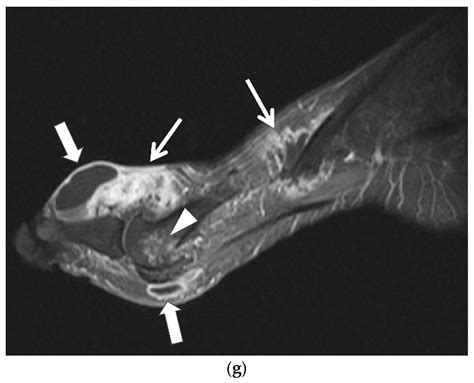

Managing gout requires a proactive, long-term approach to keep uric acid levels within a healthy range. This often involves daily maintenance medication, such as xanthine oxidase inhibitors (e.g., allopurinol), which are prescribed to lower uric acid production. Equally important are lifestyle modifications, including maintaining a healthy weight, exercising regularly, and adopting a diet low in high-purine foods. By working closely with a rheumatologist, you can develop a personalized plan that minimizes the frequency of attacks and protects your hand joints from long-term damage caused by crystal deposits, known as tophi.